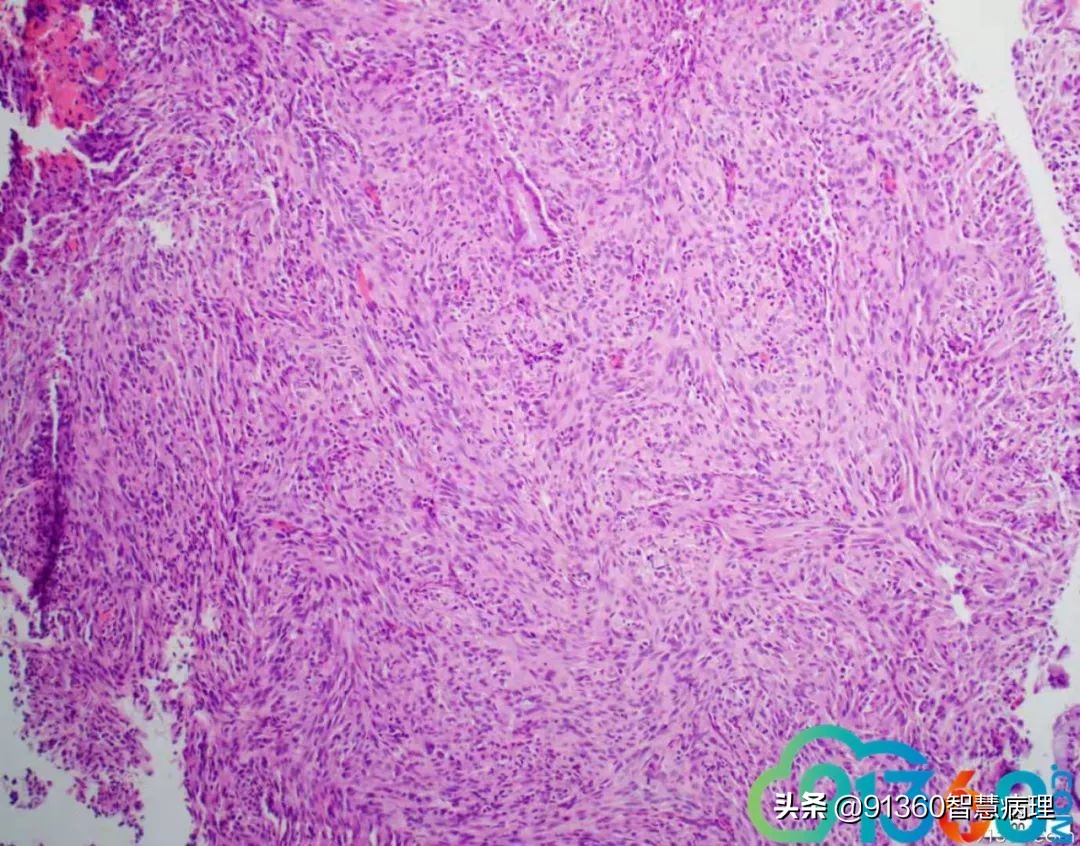

邢德印 Desmin -Sarcomatoid carcinoma; spindle cell carcinoma 石岩 @邢德印(妇科病理) 好例子 邢德印 以前没见过这么明显的,太肉瘤样了 任永昌 @邢德印(妇科病理) 赞 郭晓静 @邢德印(妇科病理) 我偏向猜的答案也是这个,。谢谢分享! 王昀 @邢德印(妇科病理) 好例子,没见过这么弥漫肉瘤样的,回过头来看,好像还是有点结构的样子

邢德印 @王昀 301 圈里的是mitosis 任永昌 @邢德印(妇科病理) @王昀 301 实际上,上边这个腺体有异型,核过于大。

王昀 哦,我说那个裂隙,有点像腺的结构 邢德印 @临沂市中心医院任永昌 @王昀 301 腺体其实是entrapped,正常的腺体 王昀 我是想起乳腺的化生性癌,所以想看看有没有腺和梭形细胞过渡移行的地方,能找点线索,可能是知道答案后开始想象了,这个可能是假腺